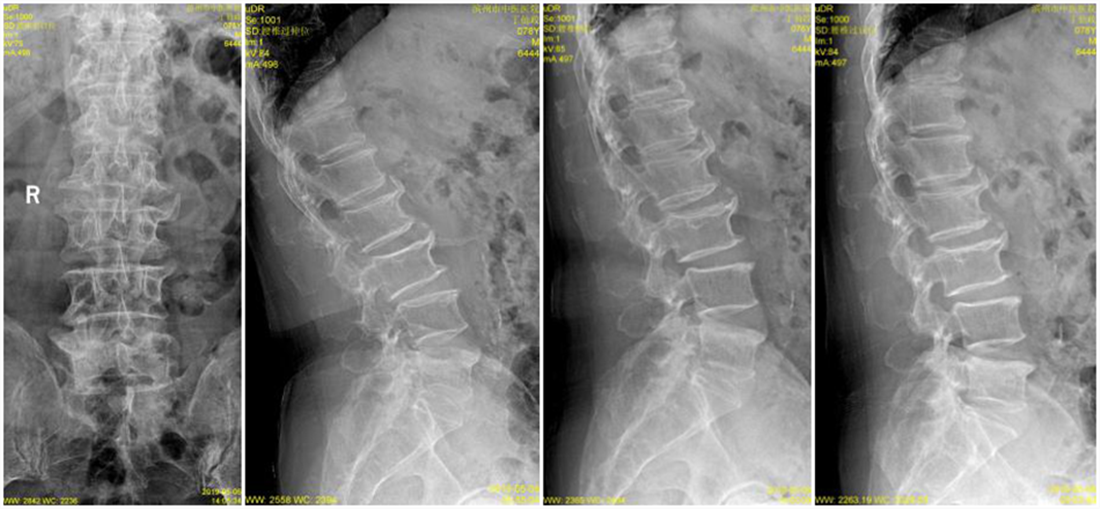

入院后经过详尽询问病史、仔细查体及全面影像检查及分析。患者存在腰部脊椎的纵向的失稳,在站立时存在椎间隙变窄,椎间盘组织进一步突出明显。针对此病患的传统理念,是行腰椎椎弓根螺钉固定加以椎间隙植骨融合术治疗,但由于该患者年龄较大,若以传统理念进行手术,对此高龄患者的创伤较大,恢复期较长。综合考虑后,决定为该患者采取椎板开窗髓核摘除术加以棘突间动态固定(COFLEX)术。

术前X线片